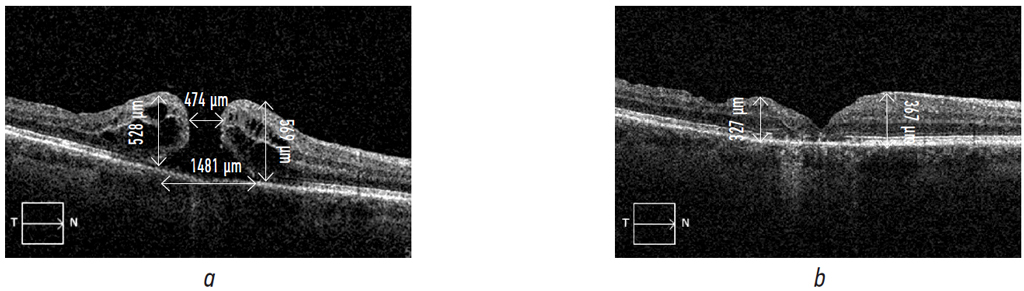

According to the data presented in the table, before surgery, in the overwhelming number of patients (85.8%), visual acuity was from 0.01 to 0.1, during the post-op period, in a significant number of patients (76.8%), visual acuity raised up to 0.2–0.3 and higher. As examples, pre- and postoperative OCT results of patients L. and G. and their visual functions are shown on Fig. 3 and 4, respectively.

Fig. 3. Patient L. Right eye: macular hole stage 4, the macular hole history is longer than a year: a — Right eye: Vis before surgery 0.09; b — Right eye: Vis after surgery 0.4

Рис. 3. Пациент Л. Макулярные разрывы правого глаза (OD) IV стадии, длительность существования макулярного разрыва (из анамнеза) более года: a — Vis OD 0,09 до операции; b — Vis OD 0,4 после операции